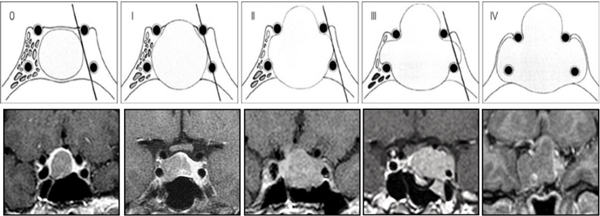

A todos los pacientes se les realizó además de la RM de hipófisis con gadolinio y con secuencia dinámica, tomografía computada (TC) de cerebro y senos paranasales para evaluación y planificación prequirúrgica. Se clasificaron los tumores según el tamaño en microadenoma (<10 mm) y macroadenoma (≥ a 10 mm) y según la escala de Knosp en no invasores (Grados 0, 1 y 2) y en invasores (Grados 3 y 4)26 (Figura 3). Fueron evaluados el resto de los ejes hipofisarios. Se consideraron las complicaciones clínicas más importantes del hipercortisolismo: HTA, DM2, obesidad, osteoporosis , trombosis venosa profunda (TVP) y trastornos psiquiátricos. Se evaluó el tratamiento farmacológico específico previo. Dividimos la serie en dos etapas comparando los primeros 20 pacientes operados con los últimos 20 pacientes (datos prospectivos) para evaluar la curva de aprendizaje.

Figura 3. Clasificación de Knosp. Invasión tumoral del seno cavernoso. Grado 0: Sin invasión del seno cavernoso. Grado 1: Sobrepasa la tangente medial (definida como la tangente que une los bordes mediales de la carótida supra e intracavernosa) pero no sobrepasa la línea tangencial que une los dos centros de la de la carótida intra-supracavernosa. Grado 2: Extensión por fuera de la línea intercarotídea, sin sobrepasar la tangente lateral. Grado 3: Extensión lateral a la línea tangencial lateral que une la porción carotídea supracavernosa con la intracavernosa. Grado 4: La carótida intracavernosa está totalmente englobada por el tumor.